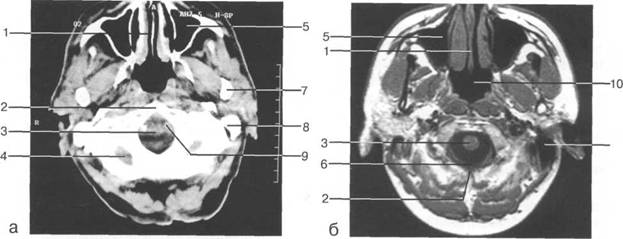

ные извилины (рис. 1.10). Структуры средней череп 13513u2010n 85;ой ямки ограничены спереди малым крылом основной кости, снизу - большим крылом, сзади - передней поверхностью пирами «edge» «bone»

Содержимое средней череп 13513u2010n 85;ой ямки представлено базальными отделами височной доли.

ристый синус с внутренней сонной артерией, череп 13513u2010n 85;о-мозговые нервы) дифференцировать тральные отделы основания череп 13513u2010n 72; занимает турецкое седло. В полости турецкого седла ви

III III III